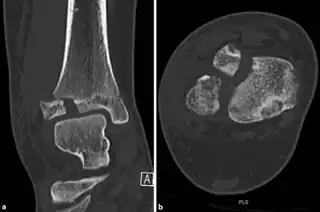

a,b)CT scan, coronal and axial plane of a Tillaux fracture in a male

CT scan